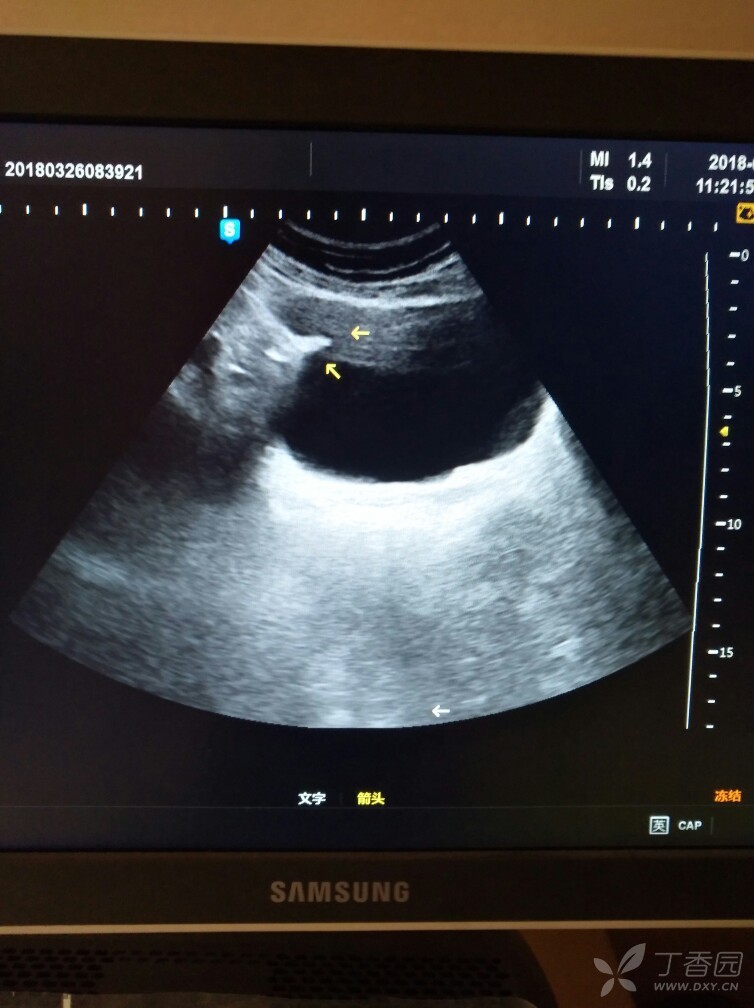

膀胱内病变 - 超声医学讨论版 -丁香园论坛

图片尺寸1280x960